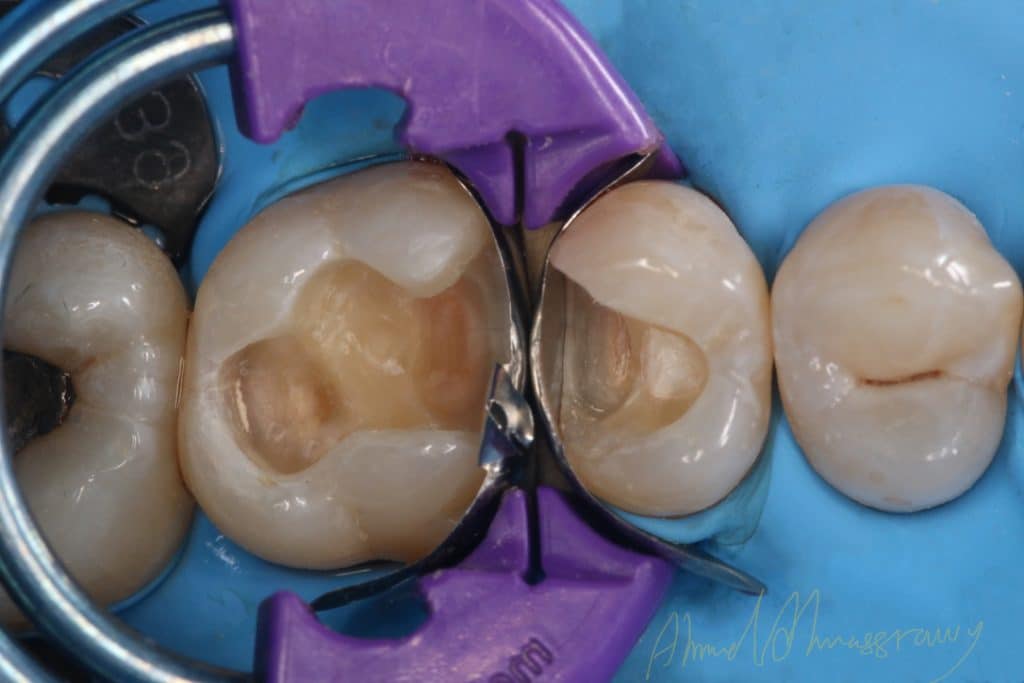

remove old restoration

cavity design

immediate dentin sealing(IDS)

Bioclear matrix system